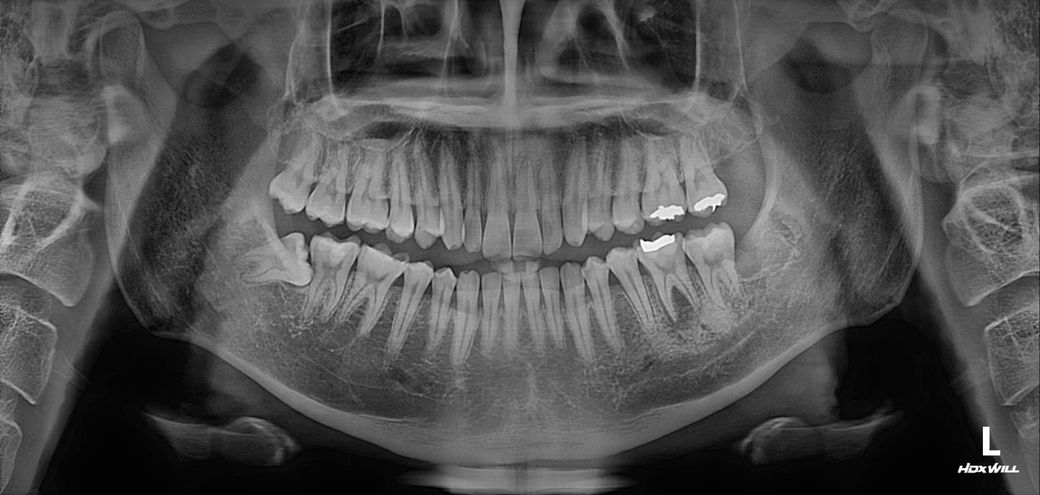

아니면 사랑니 때문인데 X선 사진 분석해주실 수 있을까요? 밑에 첨부파일로 남겨놓겠습니다.

다만 지금 엑스레이 사진상으로 오른쪽 아래 이전에 치료(떼운 치료)받은 게 신경이랑 아주 근접하긴 합니다. 치수염이 유발되는 상황일 수도 있습니다.